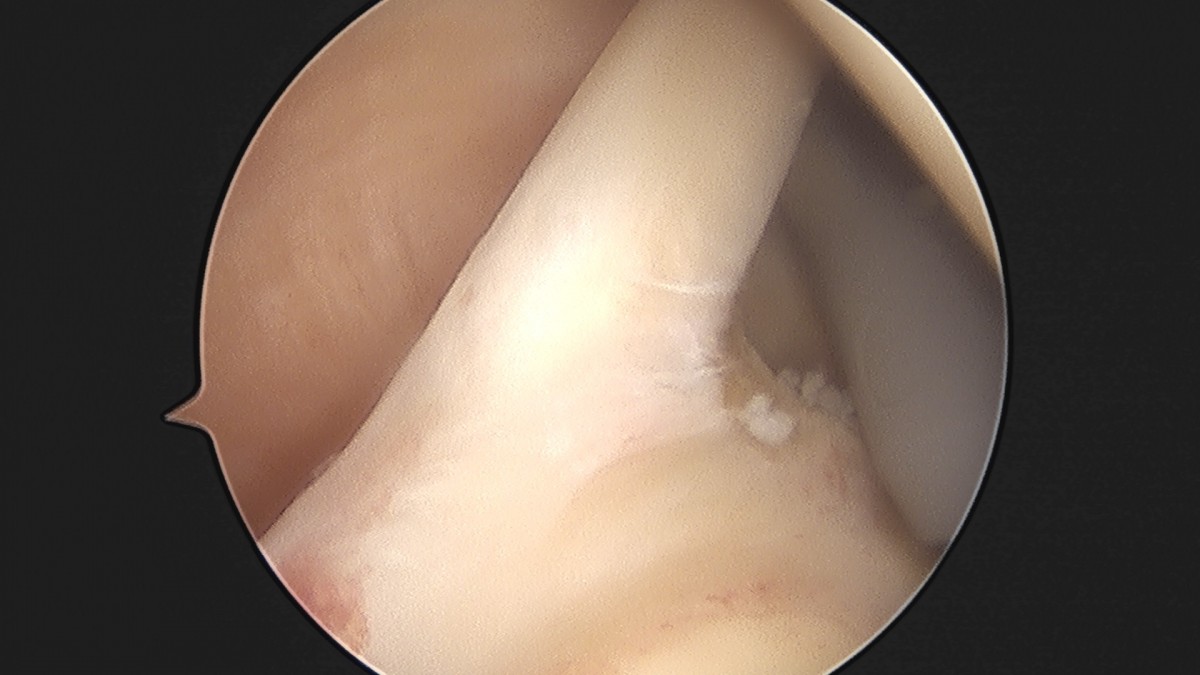

이재상원장님 어깨 석회 제거술 조광O 환자

dae765e4d9ac96aee867c9d6292d8784_1758004693_1483.jpg